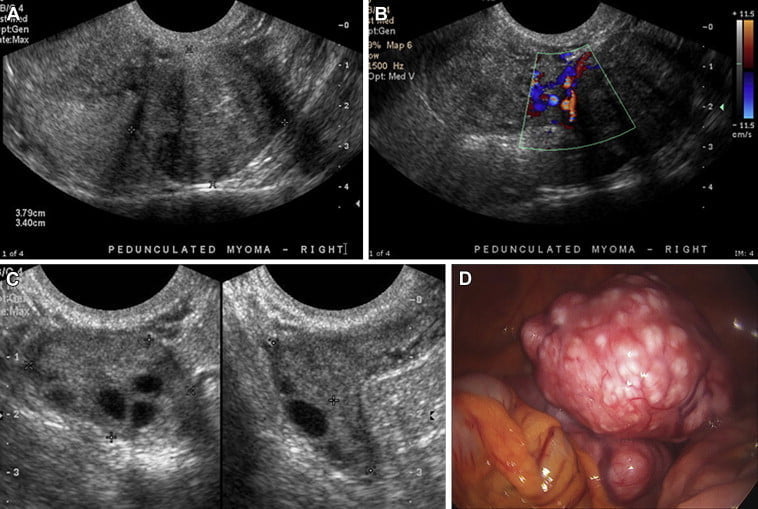

Miyomlar, rahim kas dokusundan gelişen iyi huylu tümörlerdir ve üreme çağındaki kadınlarda sık görülebilir. Çoğu miyom başlangıçta belirti vermez, ancak bazen adetlerde aşırı kanamaya, kasık ...